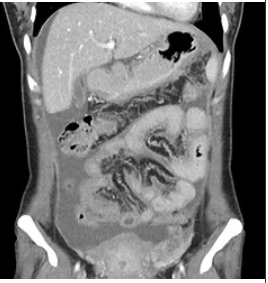

Stomach or gastric cancer is a top 10 cancer in Singapore from the Singapore Cancer Registry publication 2008 to 2012. It affects males more than females, and usually after 50 years old. Chinese ethnicity is at a higher risk compared to Malays or Indians in the registry data. However, the incidence over the years is decreasing. Some countries like Japan, have an established screening program because of the high incidence of gastric cancer. Common symptoms at initial diagnosis are weight loss and persistent abdominal pain, although it is emphasized that not all weight loss is due to stomach cancer. Some people might wonder, “Is my weight loss due to stomach cancer?”  It is often not easy to differentiate as an upper gastrointestinal endoscopy is needed to visualize the stomach and if needed a biopsy is taken. Barium studies are sometimes performed but a biopsy would have to be done separately if suspicious findings are seen.

Gastric cancer types Although lymphoma (such as diffuse large cell lymphoma or MALT lymphoma) , gastrointestinal stromal tumour (GIST) and other less common types can arise from the stomach, primary stomach cancer usually refers to carcinoma arising from the lining of the stomach and are of 2 main histopathological types (Lauren’s Classification) : Intestinal type (well differentiated) Diffuse type (undifferentiated)

Although pancreatic cancer is uncommon, it is the 5th most frequent cause of cancer deaths in Singapore and one of the top 10 most deadly cancers worldwide. There are several types of pancreatic cancers, with the majority affecting the area of the pancreas that produces enzymes. This is known as pancreatic ductal carcinoma. The pancreas also has hormone making cells (for example islet cells produce insulin). Cancers can arise in these cells and are known as neuroendocrine tumours (NET).  This article covers the more common pancreatic ductal carcinoma.